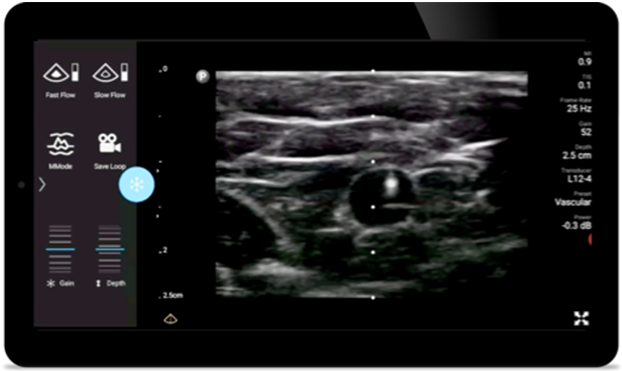

Lumify Handheld-Ultraschall für die Anästhesiologie unterstützt die klare Konturdarstellung bei der Nadelplatzierung, einschließlich der umgebenden Nerven, Gefäße und Faszienstrukturen.

Lumify kann am Patientenbett ein wertvolles Hilfsmittel sein, um den Status des Mageninhalts zu ermitteln und das Risiko einer Lungenaspiration zu senken. Dadurch lässt sich wiederum mitunter das Risiko von Anästhesiekomplikationen reduzieren.

Mit hoher Detailgenauigkeit und hervorragender Gewebedefinition aus verschiedenen Winkeln unterstützt Sie Lumify zuverlässig bei der klinischen Entscheidungsfindung in allen Versorgungsphasen.